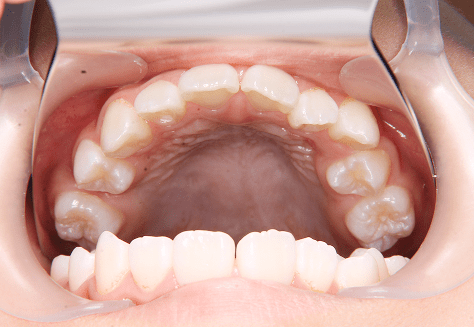

M.U

治療前

治療後

主訴

下の歯が特にガタガタなのが気になる。上の前歯が1本反対になっている。

診断

下顎前突・叢生・反対咬合

年齢/性別

20代/男性

抜歯部位

非抜歯

使用装置

上下インビザライン(PBM使用)

保定装置

ビベラリテーナー

料金

初回資料採得・・・・・・・30,000円

診断料・・・・・・・・・・33,000円

動的治療終了時資料採得・・5,500円 -

基本料金

950,000円

診察料金

5,500円×16回

治療期間

1年7カ月